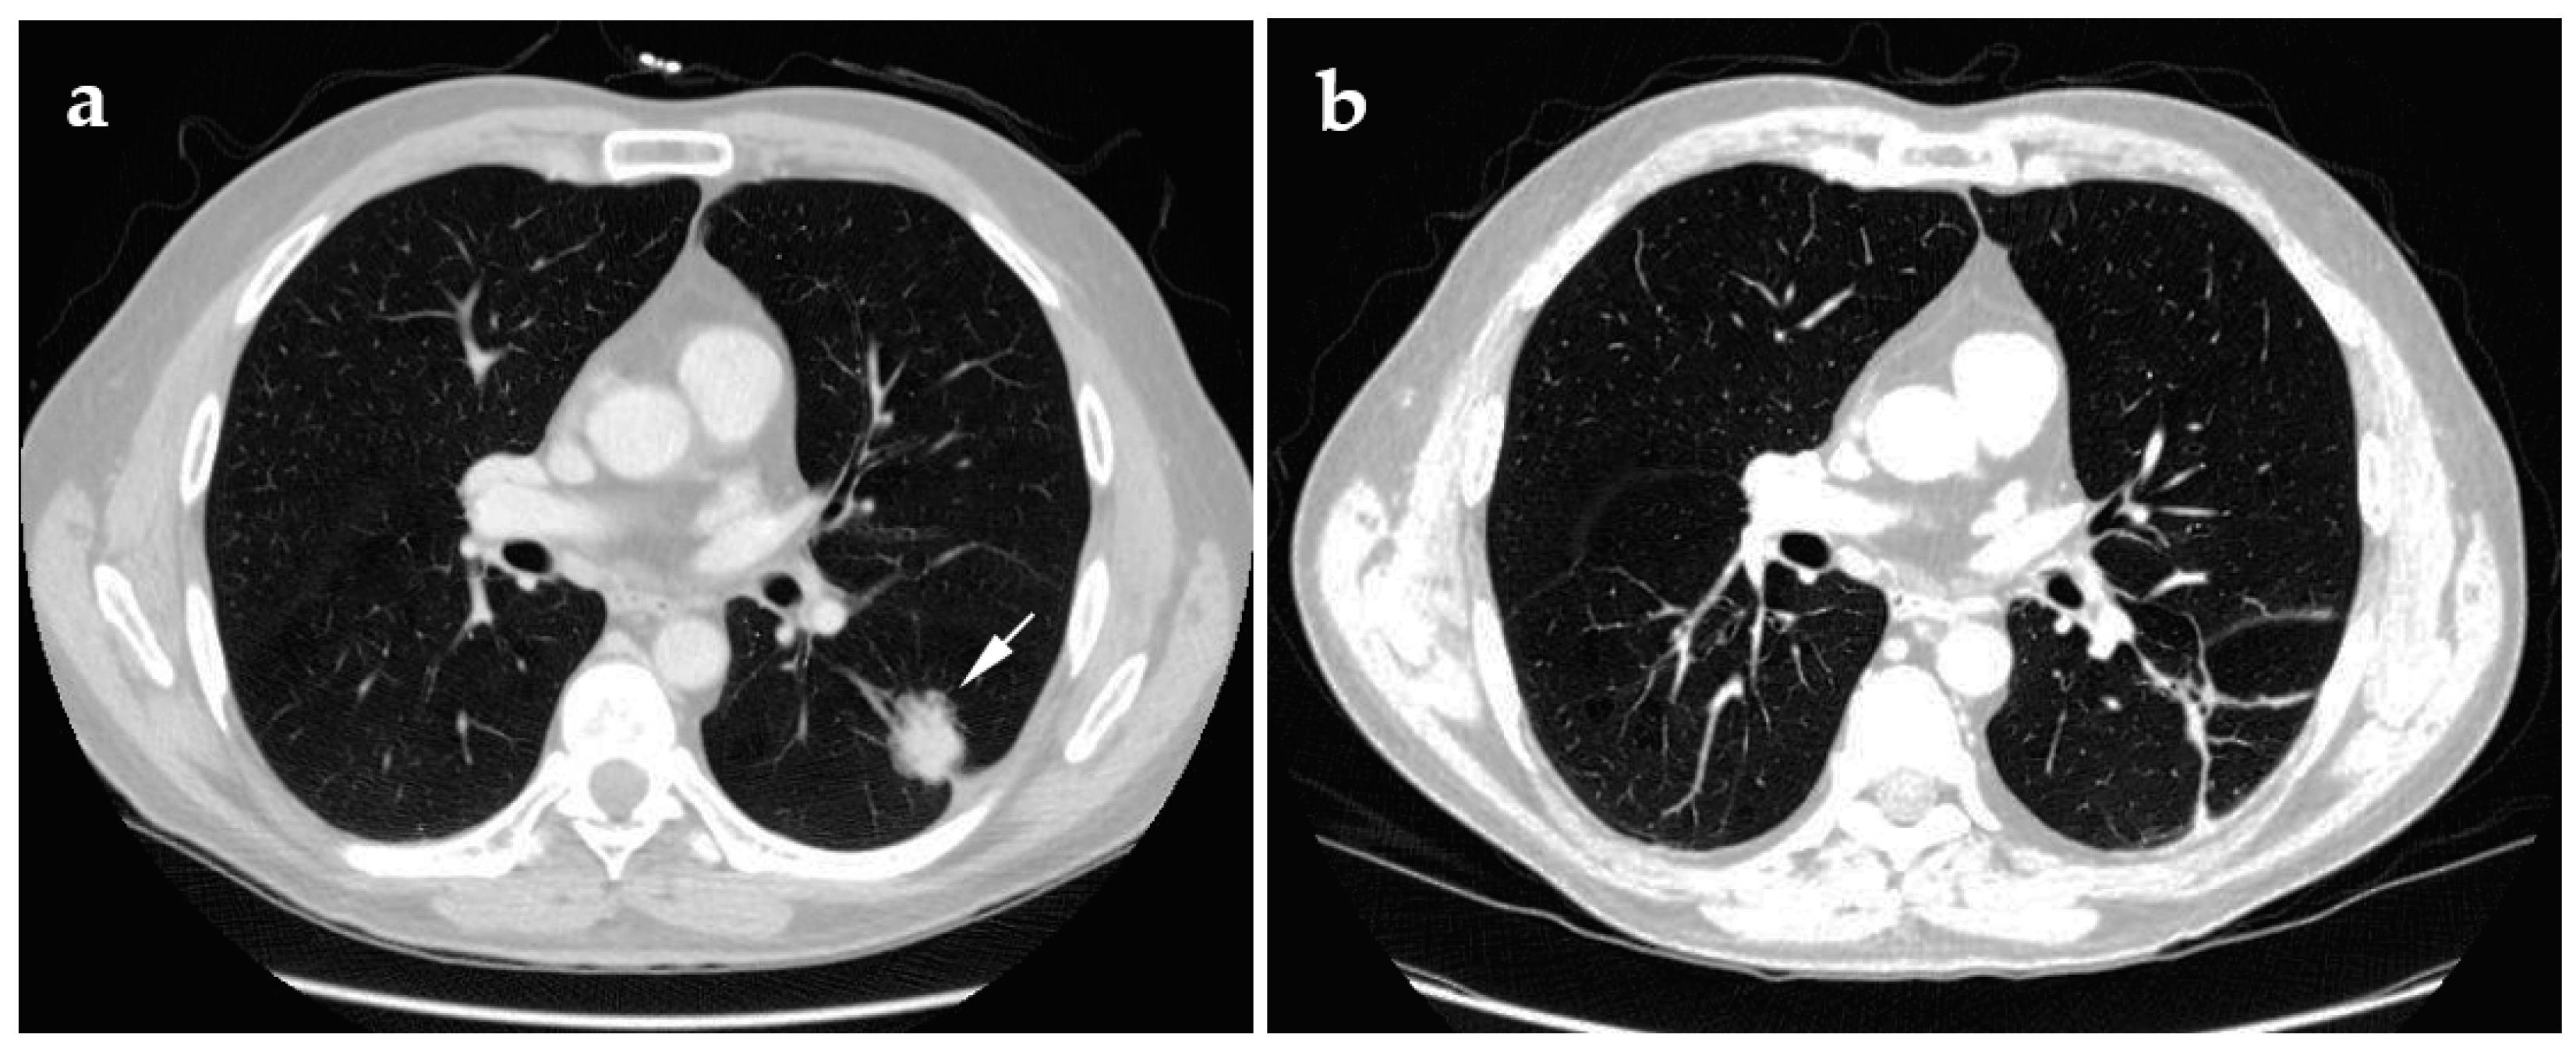

4.1. Cryoablation